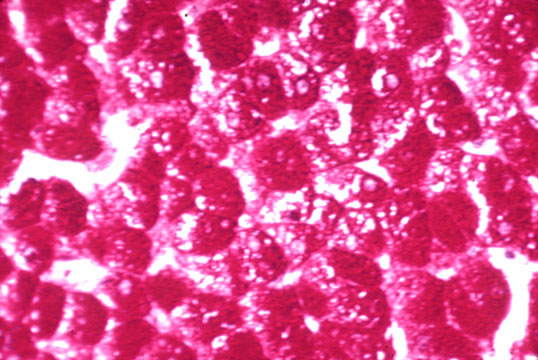

Ground glass cells in a carrier of B hepatitis

Fig 33 - GROUND GLASS HEPATOCYTES (1): Cells with a homogenous cytoplasm similar to ground glass easily spotted on H&E stain.They are seen most frequently in carrieres of HBV infection where there is marked accumulation of HBV surface antigen i the endoplasmic reticulum.. Immunostain for HBVsAg will be positive.The ground glass change,however, may occur in cases treated with various drugs which produce hyperplasia of the endoplasmic reticulum,such as barbiturates,diazepam,methotraxate, etc In this instance ,the cells are called induction cells.(2)

(1)Adziyannis,Arch.Path.96:327,1973

(2) Klinge O,Bannasch P:Verh Dtsch Ges Pathol,53:658,1968